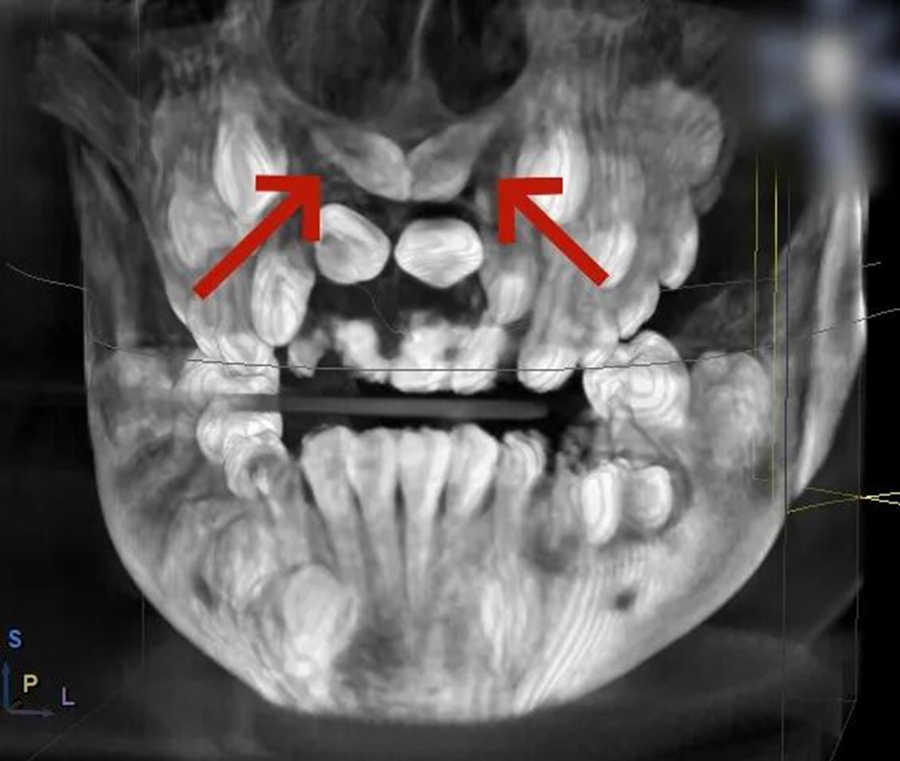

小胡已經(jīng)9歲了,本該完成換牙的“新門牙”卻遲遲沒有萌出的跡象。家長帶著他來到青島市婦女兒童醫(yī)院檢查,拍攝 X 光片后發(fā)現(xiàn),小胡的上頜骨內(nèi)竟然埋伏著2顆多生牙,這兩顆 "不速之客" 橫著長在門牙牙根處,位置高至鼻底,還伴隨唇向傾斜,阻礙了恒中切牙的正常萌出。

術(shù)前,醫(yī)生通過 CBCT 掃描獲取患者頜骨的精準立體影像,清晰定位埋伏牙的位置、形態(tài)以及與周圍血管、神經(jīng)的關(guān)系;隨后在電腦上進行虛擬手術(shù)設(shè)計,規(guī)劃出最佳的拔除路徑,巧妙避開重要組織;最后通過 3D 打印技術(shù),定制出完全貼合患者口腔結(jié)構(gòu)的導板。這塊小小的導板,就像是為手術(shù)鉆頭安裝了 "GPS 導航",能在術(shù)中精準引導器械方向,讓拔牙過程變得微創(chuàng)、安全、高效。

口腔團隊經(jīng)過全面評估和分析,最終為小胡確定了 3D 數(shù)字化導板引導的手術(shù)方案。

牙支持式定位導板